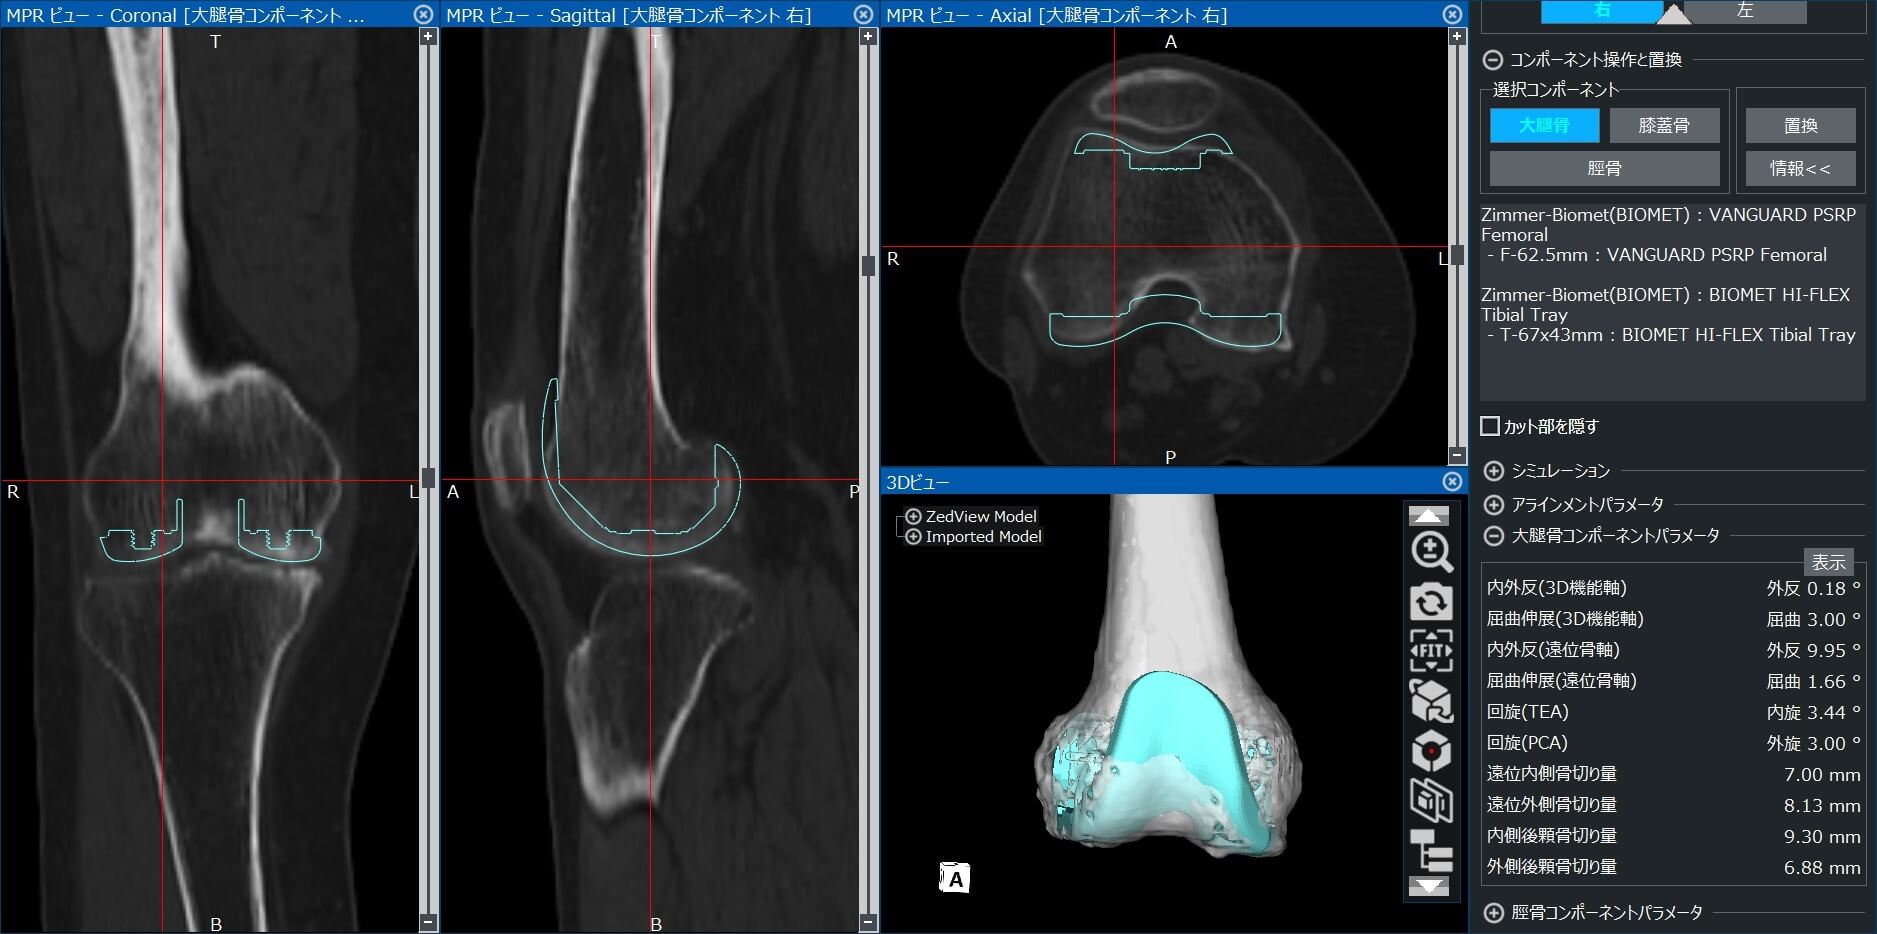

CTから作成した3D画像データを用いた術前計画

術前の撮影したCTデータより、専門のソフトを用い3Dで術前計画を作成し、一人一人に適合した人工関節を選択します。

△人工膝関節置換術 術前計画

当院の人工膝関節置換術の特徴として、バランスを整える手術方法 (Gap technic)で行っています。また、安定性の高いインプラント(ZIMMER BIOMET社 VanguardPSRPや、京セラ社Physio-Knee等)を使用しています。